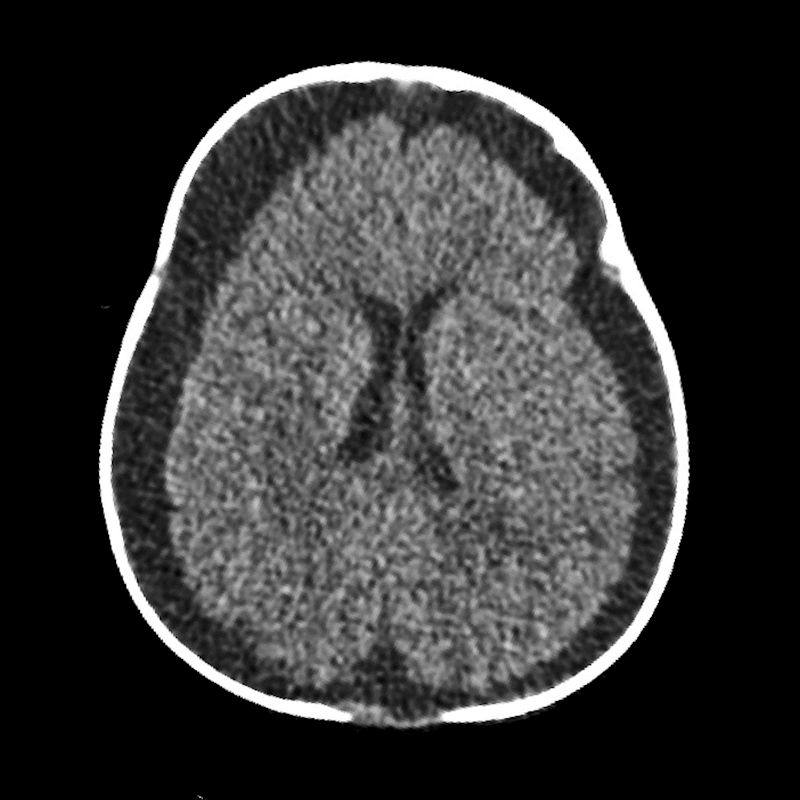

- A) Bilateral serebral konveksitede subdural higroma

- E) Subdural hematohigroma ile uyumlu yoğun içerikli bileşenler

- Subdural hematom: En sık görülen radyolojik bulgudur, vakaların %83-90’ında saptanır. Genellikle bilateraldir ve farklı yaşlarda hemorajik elemanlar içerir.

- Subdural higroma: Araknoid yırtıklara bağlı gelişir. Köprü ven yaralanması ile birlikte olduğunda hemorajik bileşenler içerebilir (hematohigroma).

- Hipoksik-iskemik yaralanma: Vakaların yaklaşık üçte birinde görülür ve prognozu en kötü olan bulgudur.